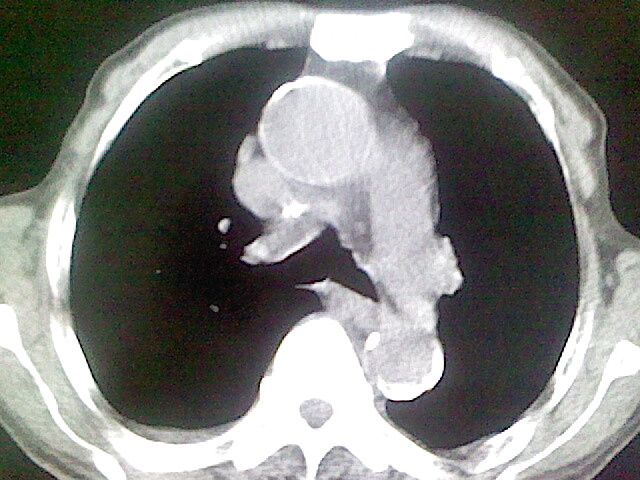

以下是引用zsl6918在2008-8-28 16:49:00的发言:[br]双肺炎性病灶,食管狭窄估计与心房增大压迫所致。

以下是引用xulianj在2008-8-28 20:36:00的发言:[br]慢支肺气肿伴感染,右上肺陈旧性结核;食道建议胃镜检查。

以下是引用wqs571018在2008-8-28 21:18:00的发言:[br]慢支继发感染,右上肺陈旧性结核;食道建议胃镜检查。